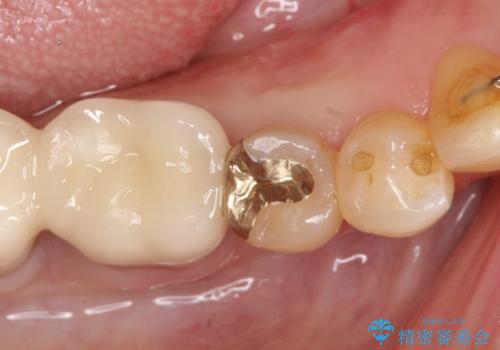

【PGAインレー】深い位置の二次カリエス

- 定期検診にて虫歯を発見したため、PGAインレーにて治療を行いました。

PGAインレーは金と白金を多く含み、精度高い修復が可能です。